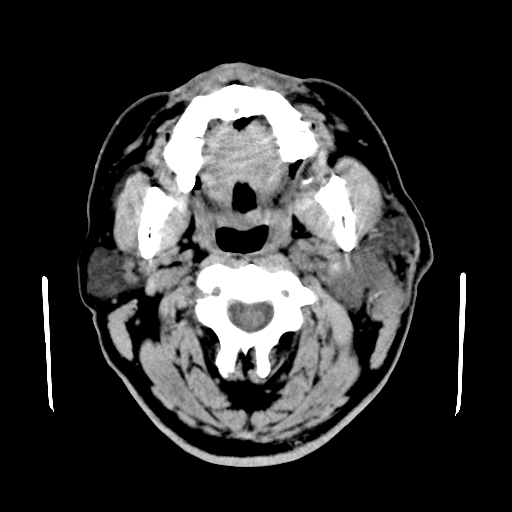

以下是引用卜一在2007-8-6 21:23:00的发言:[br]定位:左侧胸锁乳突肌内侧 颌下腺下后方。特征:弥漫性生长 软组织密度肿块,界限不清,内隐约见低密度坏死。考虑:神经源性肿瘤或血管源性肿瘤。

以下是引用wangzhanshuang在2007-8-6 21:08:00的发言:[br]腮腺混合瘤